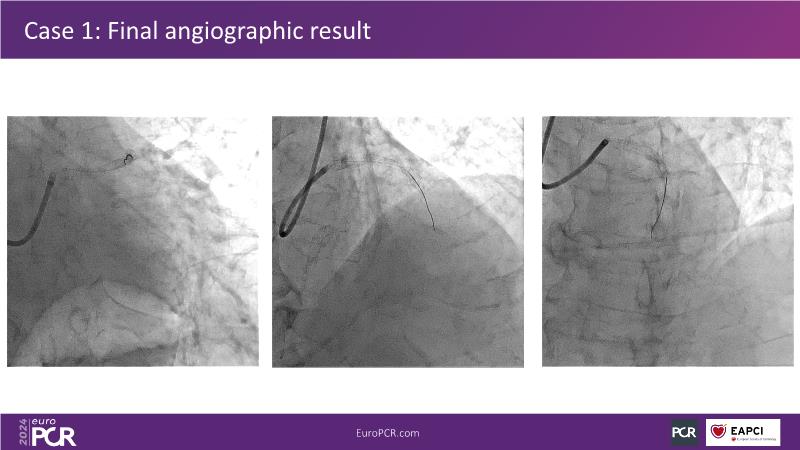

PCI in patients with diabetes: next generation DES + DCB stent platform in action

Watch this session on PCI in diabetic patients to learn about a groundbreaking technology addressing the complexities of this critical subgroup. Discover the next-generation DES and DCB stent platform and the innovative Envisolution technology behind it. Understand how it works, its advantages in managing complex cases, and what sets it apart from other technologies. Gain insights into the future of polymer-free DES + DCB stent technology and its potential impact on patient care.